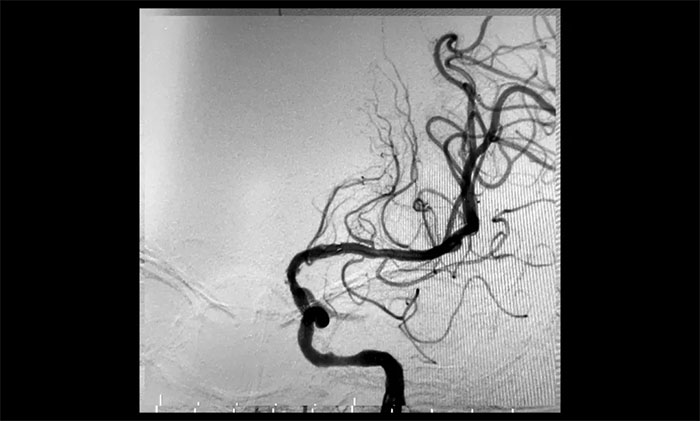

患者為老年男性,因言語不利,伴右側肢體活動不利入院。外院行頭顱CT檢查:雙側腦室旁及基底節(jié)區(qū)腔隙灶。入院后,頭顱MRI平掃+DWI+MRA提示,腦干、雙側小腦及雙側大腦半球多發(fā)腔梗、缺血灶;MRA:腦動脈硬化,左側頸內(nèi)動脈不完全閉塞,右側頸內(nèi)動脈C3-C6段、右側大腦中動脈M2段多發(fā)狹窄。“主動脈弓+全腦動脈造影”提示:右頸內(nèi)動脈起始段重度狹窄,左頸內(nèi)動脈起始段重度狹窄,串聯(lián)左頸內(nèi)動脈巖骨段中度狹窄,左頸內(nèi)動脈眼動脈段閉塞。

▲ 左頸內(nèi)動脈起始段重度狹窄,并串聯(lián)多處狹窄、閉塞

術后一個月,經(jīng)過綜合治療,患者病情穩(wěn)定。10月11日,再次行經(jīng)皮左側頸動脈慢性閉塞開通術,腦保護傘下左側頸動脈支架置入手術,經(jīng)皮左側頸動脈球囊擴張成形術。術中造影顯示,左頸內(nèi)動脈起始段多發(fā)重度狹窄,左頸內(nèi)動脈前向血流慢,左頸內(nèi)動脈巖骨段中度狹窄,左頸內(nèi)動脈眼動脈段、后交通段多發(fā)重度狹窄伴次全閉塞。

經(jīng)微導絲成功進入狹窄、閉塞頸內(nèi)動脈,在支架保護下,進行球囊逐段擴張,支架置入……,經(jīng)多次球囊擴張,置入支架后,造影顯示左頸內(nèi)動脈起始段狹窄明顯改善,左頸內(nèi)動脈顱內(nèi)段順利再通,左頸內(nèi)動脈眼動脈段、后交通段狹窄明顯改善。造影及3D造影見左頸總動脈、左頸內(nèi)動脈、左大腦中動脈顯影可,行支架CT見顱內(nèi)支架成形可,手術取得成功!

▲術后,左頸內(nèi)動脈起始段狹窄明顯改善,左頸內(nèi)動脈顱內(nèi)段順利再通,左頸內(nèi)動脈眼動脈段、后交通段狹窄明顯改善